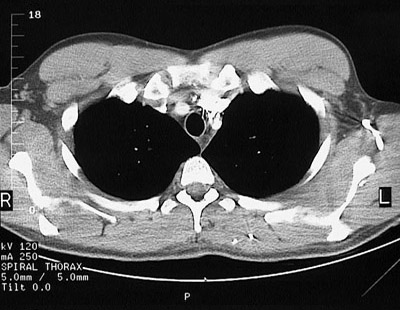

[T3] This is a normal chest CT scan demonstrating the right lung and left lung and pectoralis major muscle and pectoralis minor muscle and left brachiocephalic vein and left subclavian vein and brachocephalic artery and sternum and clavicle and trachea and subscapularis muscle and spine of scapula and infraspinatus muscle and trapezius muscle and rhomboid major & minor muscle and transversospinal muscle in the upper chest.